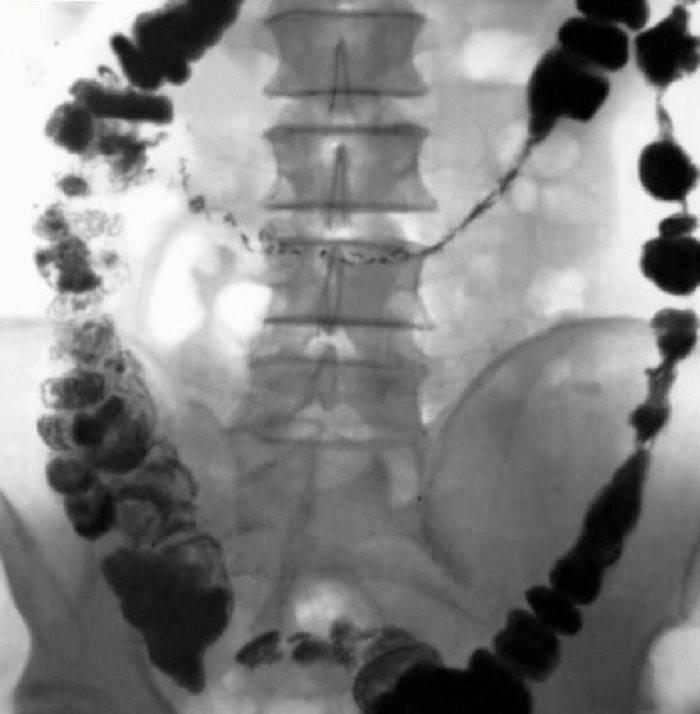

Термин «лаваж» в медицине применяется довольно давно. В переводе с латинского означает промывание, орошение какой-либо полости организма. В данном случае мы говорим о промывании желудочно-кишечного тракта. Этот способ был разработан в институте Склифосовскогов начале 80 годов для лечения больных с острыми отравлениями химическими веществами. В то время не было достаточно эффективных и безопасных способов полного очищения организма.

Дело в том, что такие методы как гемосорбция, гемодиализ и плазмаферез позволяют очистить только кровь, а большая часть вредных веществ находится в пищеварительном тракте. И тогда был разработан раствор, который без последствий очищает не только желудочно-кишечный тракт, но также кровь и лимфу.

Очищение организма производится раствором, сбалансированным по всем макроэлементам, необходимым нашему организму. Он содержит натрий, калий, кальций, фосфор, серу, магний, хлор, углерод. Нет только азота. Это дает возможность избежать опасных последствий. Как известно, химическое и физическое состояние внутренней среды кишечника отличается постоянством и не зависит от характера питания. Если в пище, когда она попадает в кишечник, не хватает каких-либо элементов, то она не будет всасываться до тех пор, пока недостающее не будет получено из крови. После промывания, например, просто соленой водой, можно получить серьезные осложнения. Солевой раствор состоит из натрия и хлора, нет других важных макроэлементов. Таким образом, если ставить перед собой задачу полного очищения организма, то недостающие вещества будут просто вымываться из крови. Это приведет к серьезным изменениям в ее составе, что может привести к тяжелым последствиям.

Специально разработанный раствор позволяет организму взять все, что нужно и отдать то, что в избытке. Избыток различных веществ возникает из-за болезненных процессов.